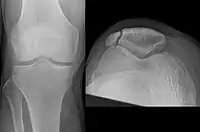

Transverse fracture of patella

Comminuted fracture of patella

Osteochondral fracture of patella- Vertical patella fracture